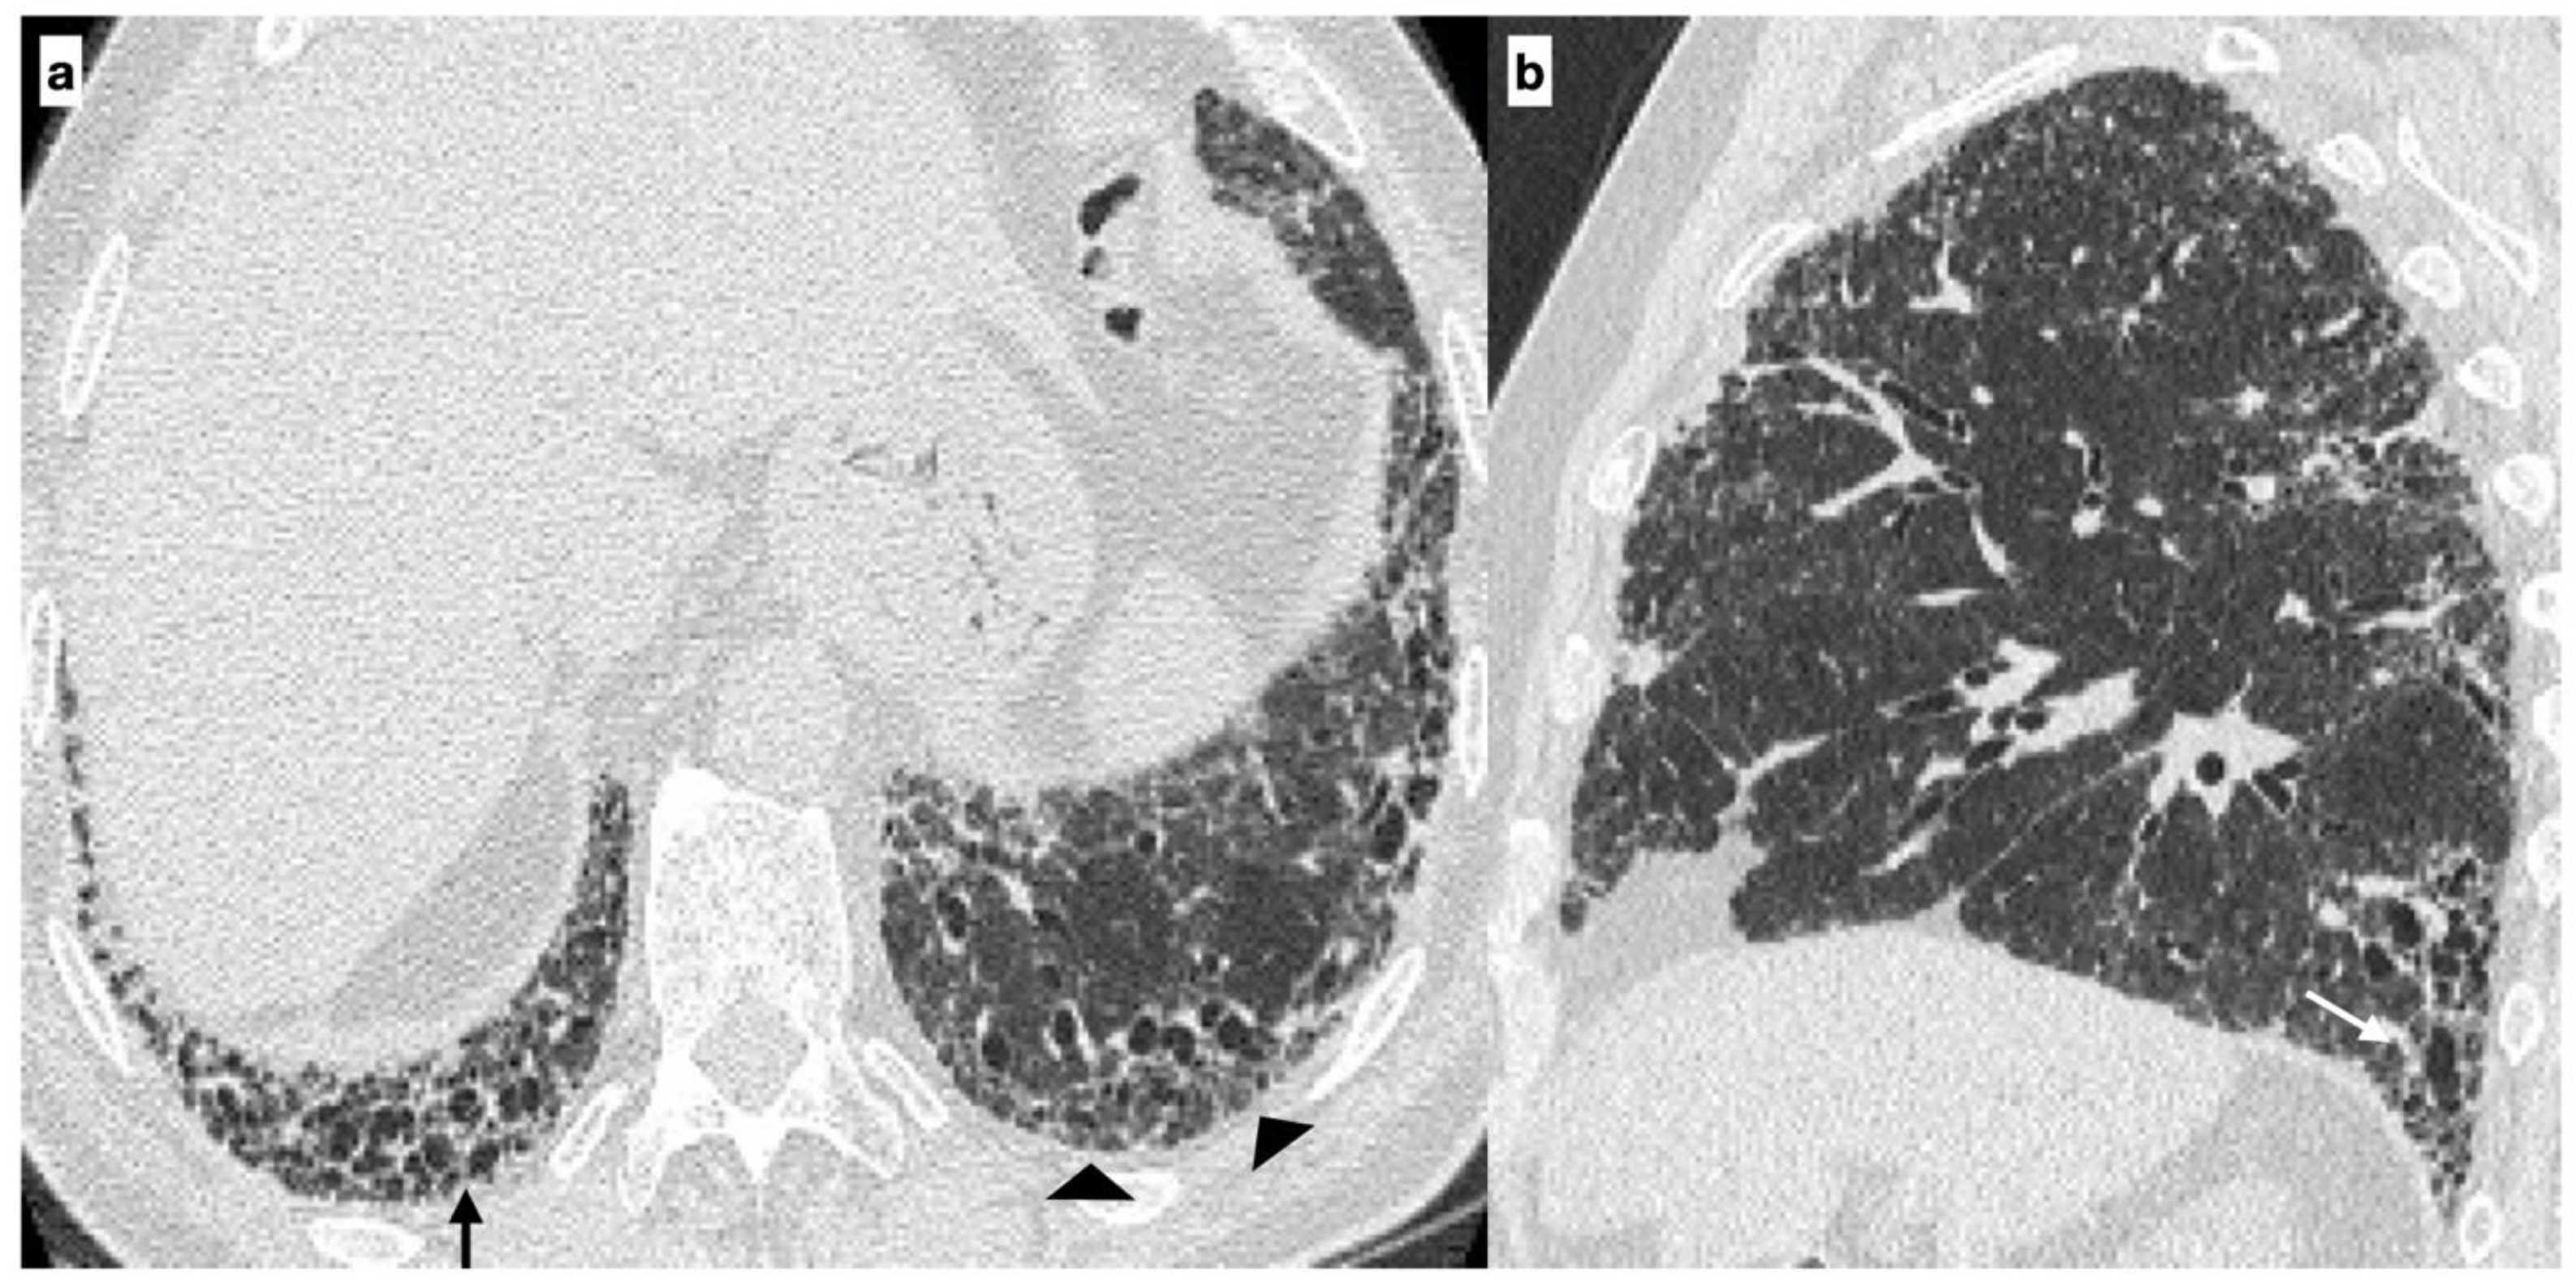

At diagnosis, there was a statistically significant difference in the HRTC pattern between the two groups: sporadic IPF patients had a predominantly typical UIP pattern compared to familial IPF patients (60.0% vs. 21.1%, respectively). There was a predominance of an alternative diagnosis HRTC pattern in familial IPF compared to sporadic IPF (31.6% vs. 2.2%, respectively) (see Figure 1, Figure 2 and Figure 3). The HRCT for 6/19 patients with a familial pulmonary fibrosis at the onset of symptoms had an alternative diagnosis pattern: this was due to the presence of a fibrotic nonspecific interstitial pneumonia (NSIP) pattern in 4/19 patients, whilst in 2/19 patients it was due to the presence of honeycombing with upper-mid lung distribution (see Figure 1). At the onset of symptoms, only 1/46 sporadic IPF patients had an alternative diagnosis HRCT pattern, due to the presence of honeycombing with upper-mid lung prevalence and mosaic attenuation; the definitive diagnosis of IPF was made by biopsy (see Figure 2 and Figure 4). After 2 years from diagnosis in the familial IPF group, we observed a slight increase in the typical UIP pattern at HRTC evaluation (see Figure 3 and Figure 5).

Figure 5. A 64-year-old male with an “Indeterminate pattern” on HRCT at onset of respiratory symptoms. The baseline axial HRCT image evidences subtle ground-glass opacities (black arrows) and reticulation (arrowheads) located in the subpleural regions of the lung bases with a predilection for the peripheral areas of both lungs (a). Follow-up HRCT, performed two years later, evidenced the worsening of the HRCT pattern due to the presence of extensive reticulations (arrowheads) and traction bronchiectasis/bronchiolectasis (white arrows) with a basal predominance (probable UIP pattern) (b). Genetic analysis demonstrated the following mutations: SFTPA2, promoter-TERT, SFTPC.

IPF patients may have more than one mutation and the number of mutations per patient averages 2.7 (min: 1, max: 5). Rare mutations were observed in our study groups, as listed in Table 2 and Table 3. MUC5B rs35705950 mutation was present in a minority of our patients and associated with a non-typical UIP pattern at HRCT scan. Two-thirds of patients with a TERT mutation at baseline had a typical UIP pattern (66.6%) (see Figure 2 and Figure 4), whilst the UIP pattern was observed in 1/15 patients without this mutation (6.6%) (p-value = 0.033). Furthermore, patients with SFTPC mutation had a frequent, but not statistically significant, indeterminate or alterative pattern (see Table 4) (see Figure 5).